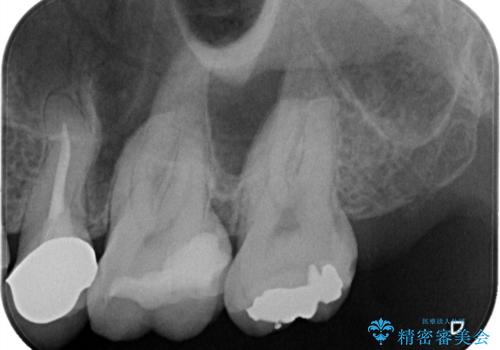

- 定期検診にて虫歯が見つかった患者様です。

金属のインレーの下と、歯と歯の間も虫歯だったため、つなげた形でセラミックインレーにて修復を行なっています。

e-max プレスインレーを用いることで、適合の良い治療ができます。